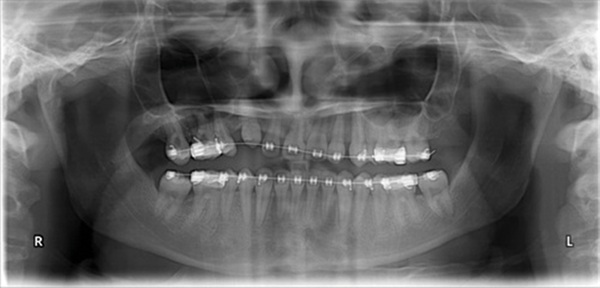

Updated records told a different story. The upper right canine remained fully unerupted, and significant adverse canting of both arches had developed on the right side (Figs. 4–6). Root shortening was visible on the upper right canine, lateral, and central incisors, likely a consequence of prior reluxation attempts to encourage eruption. The upper incisors had also become markedly more proclined over the course of treatment, a known risk when ectopic canines prove resistant to traction. Comparing the pre-treatment and current lateral cephalometric radiographs illustrated just how much incisor angulation had shifted (Figs. 2, 10). Facial photographs suggested some lower-third asymmetry with a right-side deviation, though the lower arch canting appeared to have partially self-corrected after vertical elastics were discontinued (Figs. 7–8).

Fig. 4

Fig. 5

Fig. 6